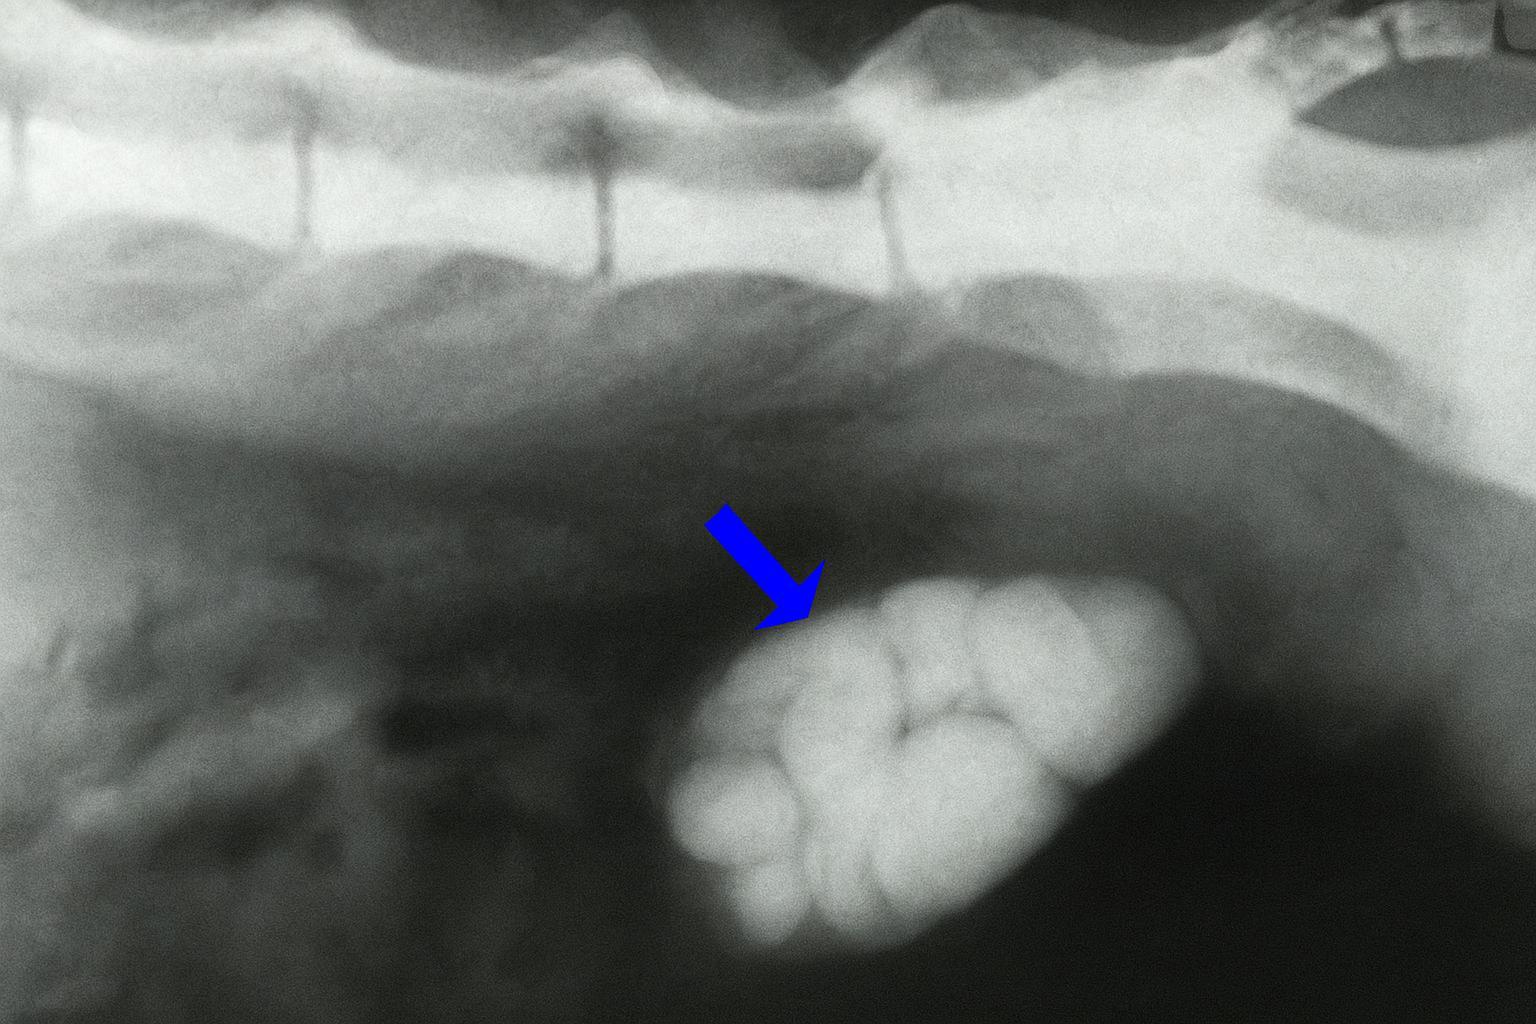

A causa mais plausível de um gato ir à caixa de areia e não conseguir urinar é a obstrução uretral, que ocorre quando algo bloqueia a uretra e impede a passagem da urina. Isso provoca seu acúmulo no organismo do gato e pode ter consequências fatais para o felino. A principal causa de obstrução são os tampões uretrais, seguidos da urolitíase ou cálculos renais:

- Tampões uretrais: são acúmulos de sangue, tecido morto, mucoproteínas ou células inflamatórias misturadas com material cristalizado, geralmente estruvita. Costumam se formar por inflamação persistente da uretra ou da bexiga, às vezes associada à CIF;

- Cálculos: são sedimentos nas vias urinárias que aparecem quando se ultrapassa o limite de certos minerais na urina, sendo os mais frequentes os de estruvita ou de oxalato de cálcio.

Se o seu gato vai muito à caixa de areia mas não faz nada devido a uma obstrução, deve-se proceder para desobstruí-lo sedando-o e utilizando um cateter urinário. Empurra-se suavemente a substância obstrutiva com soro fisiológico em direção à bexiga, mas sem exercer muita pressão para evitar danificar a uretra. Uma vez eliminada a obstrução, deve-se enxaguar a bexiga com soro fisiológico até que o líquido obtido seja transparente.

Se a obstrução for devido a urólitos de estruvita, indicas-se uma dieta urinária para dissolvê-los. Por outro lado, se forem cálculos de oxalato de cálcio, a única solução é a extração por meio de cirurgia. Além disso, a hipercalemia deve ser tratada por meio de fluidoterapia ou gluconato de cálcio a 10%, monitorizando sempre o gato com um eletrocardiograma.